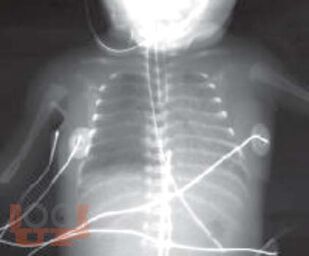

В данном томе многотомного руководства по детским болезням рассмотрены актуальные вопросы пульмонологии, систематизированные в виде современных представлений о заболевании органов дыхания. Приведены новейшие теоретические и клинические данные по анатомо-функциональной характеристике, этиологии, патогенезу, эпидемиологии, патоморфологии, патофизиологии, классификации заболеваний. Представлены методы диагностики и дифференциальной диагностики в детской пульмонологии. Даны практические рекомендации по лечению отдельных форм пульмонологических заболеваний и проведения реабилитационных мероприятий. Руководство иллюстрировано фотокопиями рентгенограмм, томограмм и др.